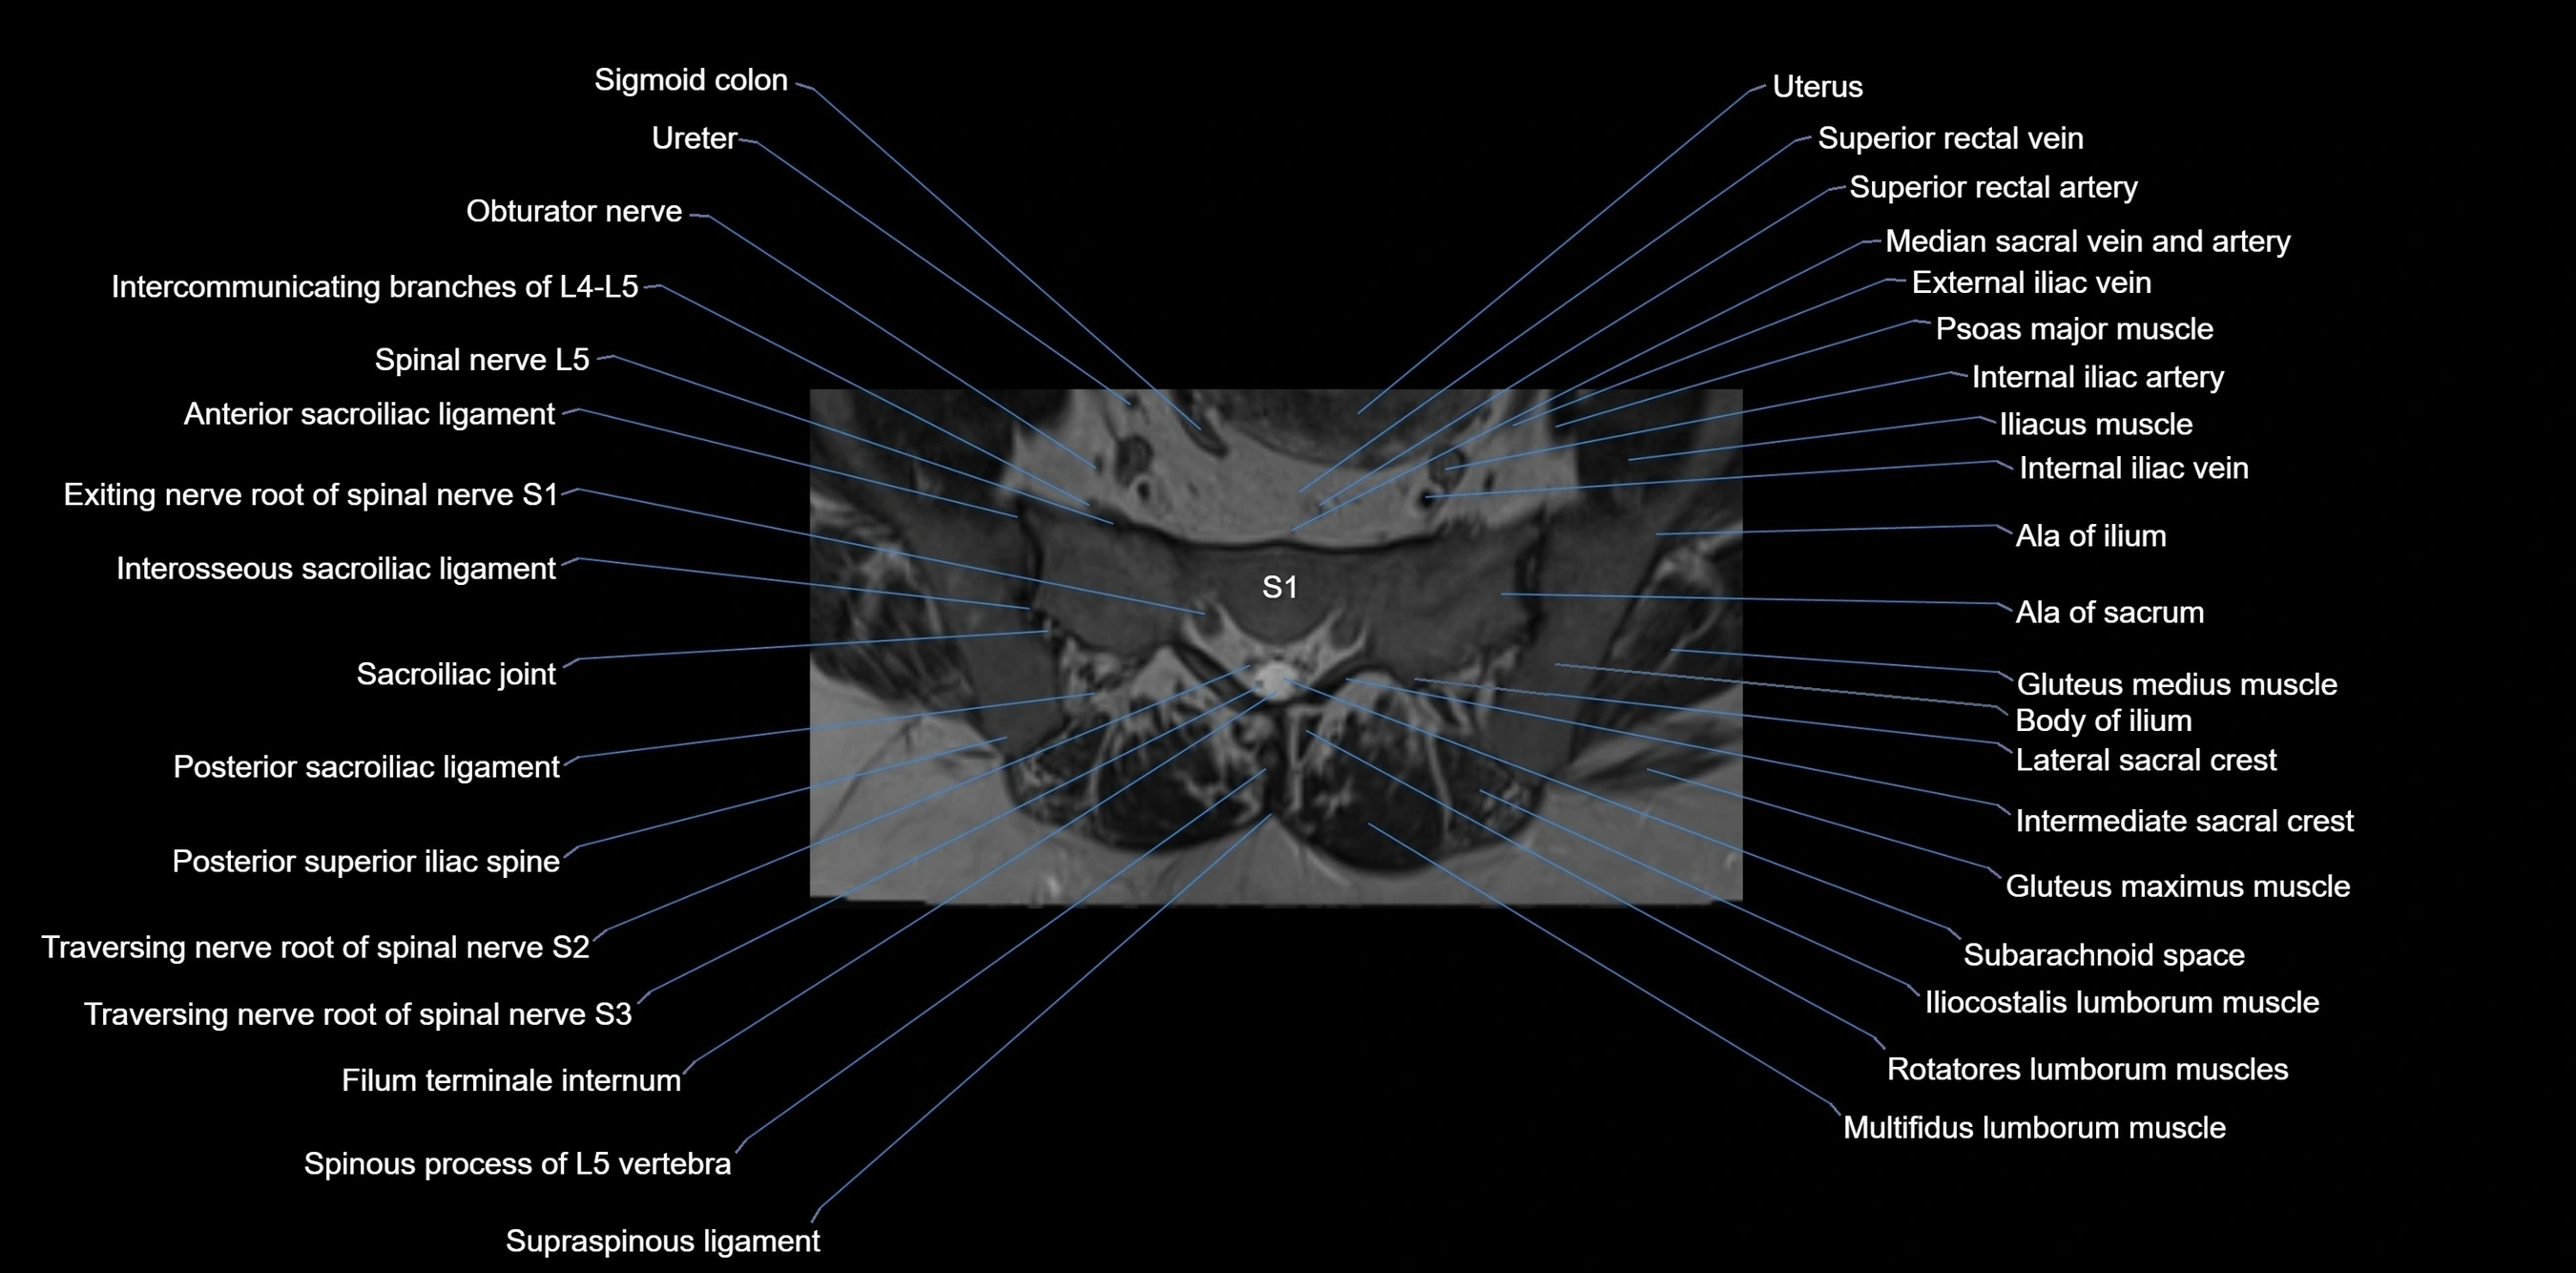

MRI Appearance

T1-weighted images:

• Cortical bone appears very low signal (dark); marrow shows intermediate signal

• Iliac fossa fat is bright against low-signal cortex

T2-weighted images:

• Cortical bone remains dark

• Marrow signal varies depending on fat content; edema or tumor shows hyperintensity

STIR:

• Suppresses fat, making bone marrow edema, fractures, or infiltrative lesions appear bright

• Excellent for trauma, sacroiliitis, and metastatic evaluation

T1 Fat-Saturated (Pre-contrast):

• Marrow: intermediate signal, fat suppressed

• Useful for detecting subtle marrow abnormalities adjacent to iliac cortex

T1 Fat-Saturated Post-Contrast (Gadolinium):

• Enhances vascularized structures, marrow pathology, tumors, and inflammatory changes

• Highlights soft tissue or bone invasion in pelvic neoplasms

MRI Non-Contrast 3D Imaging:

• Provides 3D morphology of iliac wing, crest, and articulations

• Used in preoperative planning for pelvic surgery and trauma reconstruction

MRI image

image